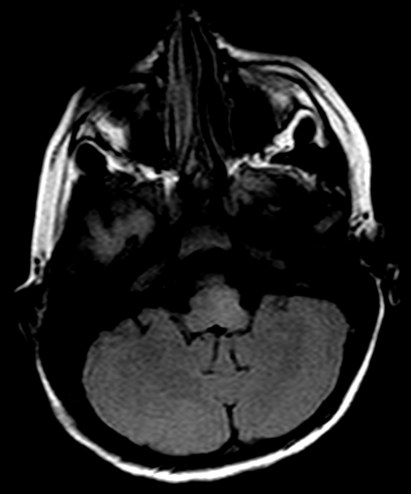

- Secuencias potenciadas en T2 y FLAIR muestran lesiones hiperintensas, de afectación bilateral, irregular, mal definidas, de tamaño variable y asimétricas que son la expresión de áreas de inflamación y desmielinización de la sustancia blanca. Las lesiones afectan sobre todo a la sustancia blanca cerebral, pero también a la sustancia gris y núcleos de la base y a médula espinal.

Las lesiones infratentoriales (incluyendo el tronco del encéfalo y la sustancia blanca cerebelosa) y las lesiones medulares son comunes, de ahí que algunos autores denominan según el área afecta encefalomielitis, cerebelitis o mielitis, siendo consideradas todas ellas variantes topográficas de una entidad común. Por ello, si no se ha realizado, es necesario realizar también una RM de columna.